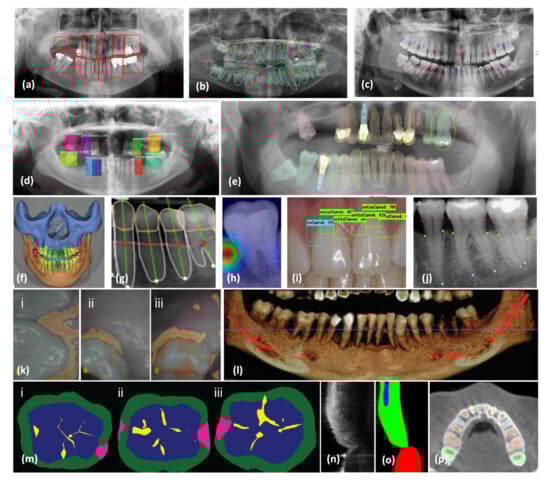

Extraoral imaging encompasses various techniques, including OCT, panoramic radiographs, Computed Tomography (CT), cone-beam CT (CBCT), and cephalometric radiographs. Among these, the panoramic radiograph is one of the most widely utilized extraoral methods in dental practices [70]. These images are employed for detecting anatomical locations, jaw pathologies, and trauma conditions [71]. CBCT, offering three-dimensional (3D) scans, has transformed dental and maxillofacial imaging in the early 21st century, providing significant advantages over two-dimensional (2D) scans in dental diagnosis and treatment planning [70,71,72]. The ability to visualize axial, sagittal, and coronal planes is a key achievement of CBCT images, which have extensive applications in dentistry, including periodontics, endodontics, dental implants, and bone pathology identification. Multiple dental imaging techniques and maxillofacial radiographs are displayed in Figure 3 [73]. This figure demonstrates the use of diverse AI models across various kinds of dental and maxillofacial imaging radiographs, highlighting their effectiveness in automated detection, segmentation, and diagnostic support [73]. Ryu et al. [74] employed Fast R-CNN for identifying periodontal bone degradation in panoramic radiographs. This framework efficiently detects regions of bone deterioration, assisting in prompt diagnosis and therapeutic strategy development (Figure 3a). Koch et al. [75] demonstrates the application of U-Net for segmenting dental panoramic radiographs. This segmentation helps in isolating different dental structures, facilitating precise analysis (Figure 3b). Kurt-Bayrakdar et al. [76] employed the U-Net framework for identifying interdental osseous loss configurations and furcation (red: vertical, blue: horizontal, and purple: furcation) as seen in Figure 3c. This approach is crucial for identifying specific patterns of bone degradation. Thanathornwong et al. [77] used Fast R-CNN for detecting periodontal compromised teeth in digital panoramic radiographs, helping in identifying teeth affected by periodontal disease (Figure 3d). De Angelis et al. [78] utilized Apox software to identify dental formulae, the existence of dental implants, prosthetic crowns, fillings, and root remnants on panoramic X-rays (Figure 3e). This comprehensive analysis aids in dental record-keeping and treatment planning. In Figure 3f, the automated segmentation of dental and maxillofacial anatomical structures is showcased using the commercially accessible AI software system, Relu (Leuven, Belgium; available at https://relu.eu (accessed on 5 December 2022)). Segmentation is essential for detailed 3D imaging and surgical planning [79]. Chen et al. [80] assessed radiographic bone loss (RBL) using deep learning on periapical radiographs for diagnosing and monitoring the progression of bone loss (Figure 3g). Figure 3h demonstrates the utilization of explainable AI (XAI) by overlaying enlarged heat maps onto single-tooth periapical images, efficiently emphasizing the active areas within the images for enhanced comprehension of AI predictions [81]. Automated tooth identification and numbering utilizing object recognition in dental periapical radiographs is depicted in Figure 3i. This automation speeds up dental charting and record-keeping [82]. Tsoromokos et al. [83] used a modified 2D-CNN for localization of the cementoenamel junction (CEJ) in red, apical extension of the alveolar crest (AEAC) in yellow, and apex (APEX) in blue in periapical radiographs, aiding in detailed dental analysis (Figure 3j). The authors of [84] highlight the power of DL models in segmentation of gingival disease in intraoral images, which is critical for diagnosing and treating periodontal diseases (Figure 3k). Figure 3l demonstrates the extent of alveolar bone deterioration and depletion of alveolar bone in a three-dimensional panoramic volumetric reconstructive CBCT scan of the mandibular arch. The red line denotes the path of the inferior alveolar nerve system, crucial for surgical strategizing [85]. Casalegno et al. [86] utilized U-Net caries detection using near-infrared light transillumination (NILT) based on different teeth. This non-invasive method enhances early caries detection (Figure 3m). Figure 3n,o present examples of OCT imaging and its volumetric segmentation, respectively. A modified CNN named OCT Image Net was used for segmentation of background, gingiva, alveolar bones, and teeth, providing high-resolution imaging for detailed analysis [87]. Cui et al. [88] introduced a framework dubbed ToothNet designed for the automated segmentation and recognition of individual teeth from CBCT images (Figure 3p).This figure comprehensively demonstrates the advancements in AI applications in dental and maxillofacial imaging, highlighting their potential in improving diagnostic accuracy and efficiency in clinical practices [89].

Figure 3.

Different AI models that have been applied on a variety of dental and maxillofacial imaging radiographs included in this study [73,89]: (a) periodontal bone loss detection using Fast R-CNN. The red boxes are the output of the model for ROI detection (reprinted from Ref. [74]), (b) panoramic radiograph segmentation with U-Net (reprinted with permission from Ref. [75], copyright (2024) IEEE), (c) detection of bone loss patterns and furcation with U-Net (reprinted from Ref. [76]), (d) periodontal compromised teeth detection using Fast R-CNN (reprinted from Ref. [77]), (e) dental formula and prosthetics detection with Apox software. The image depicts various dental components, including dental formulas, implants, prosthetic crowns, fillings, root remnants, and root canal treatments (reprinted from Ref. [78]), (f) CBCT image segmentation with Relu software (reprinted from Ref. [79]), (g) bone loss assessment with DL models (reprinted from Ref. [80]), (h) XAI heat maps on periapical images (reprinted from Ref. [81]), (i) a deep learning-based approach for the detection of early signs of gingivitis in orthodontic patients using faster region-based convolutional neural networks (reprinted from Ref. [90]), (j) CEJ, AEAC, and APEX localization using Modified 2D-CNN (reprinted from Ref. [83]), (k) gingival disease segmentation. Examples of segmentation results on the validation set are shown in i–iii (reprinted from Ref. [84]), (l) 3D CBCT image reconstruction showing bone loss (reprinted from Ref. [85]), (m) caries detection with U-Net. Examples of segmentation results on the validation set are shown in i–iii (reprinted from Ref. [86]), (n) an example of a OCT image (reprinted from Ref. [87]), and (o) its segmentation with OCT Image Net (reprinted from Ref. [87]), (p) tooth instance segmentation from CBCT images using ToothNet (reprinted from Ref. [88]).